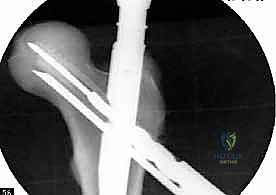

1. المسمار النخاعي الرئيسي (Intramedullary Nail): مسمار طويل يمتد داخل القناة النخاعية لعظمة الفخذ.

2. المسمار الرأسي/العنقي (Cephalic/Lag Screw): مسمار سميك وقوي يمر من خلال الجزء العلوي للمسمار النخاعي، ويدخل في عنق ورأس عظمة الفخذ لتثبيت الكسر الرئيسي.

3. مسامير الغلق السفلية (Distal Locking Screws): مسامير صغيرة تُثبت أسفل المسمار النخاعي لمنعه من الدوران أو الانزلاق داخل العظم.

هذا التصميم العبقري يجعله أقوى نظام تثبيت متوفر حالياً، حيث يمر محور تحمل الوزن عبر المسمار الموجود داخل العظم، مما يجعله مقاوماً للكسر والانحناء، ويسمح للمريض بالاعتماد على ساقه في وقت قياسي.

5. تثبيت عنق ورأس الفخذ (المسمار الرأسي)

من خلال ذراع توجيه متصلة بالمسمار الرئيسي، يتم إحداث ثقب في عنق ورأس عظمة الفخذ. يتم إدخال المسمار الرأسي (Cephalic Screw) السميك ليمسك برأس الفخذ بقوة ويسحبه نحو المسمار الرئيسي، مما يضغط الكسر (Compression) ويحفز التئام العظام بسرعة.